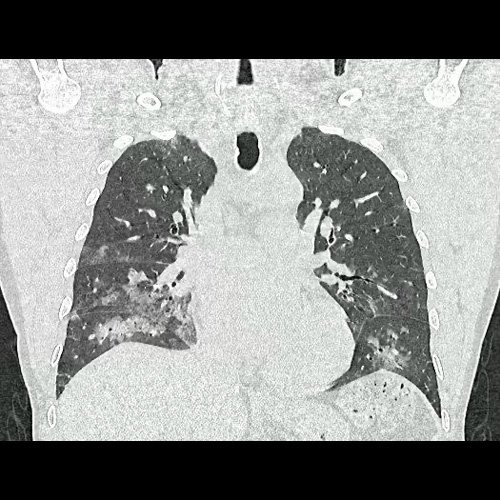

• Tomografía de tórax sin contraste endovenoso (Dia 0):Se observan múltiples áreas de consolidación parenquimatosa con broncograma aéreo y de distribución difusa por ambos pulmones, predominando en los lóbulos inferiores, asociadas a engrosamiento de los septos y rodeadas de tenue vidrio esmerilado. Se identifican estructuras ganglionares lateroaórticas, pretraqueales y subcarinales, ninguna de ellas sin alcanzar rango megálico.

Tomografia de torax sin contraste endovenosos (Ventana pulmonar- Corte coronal)